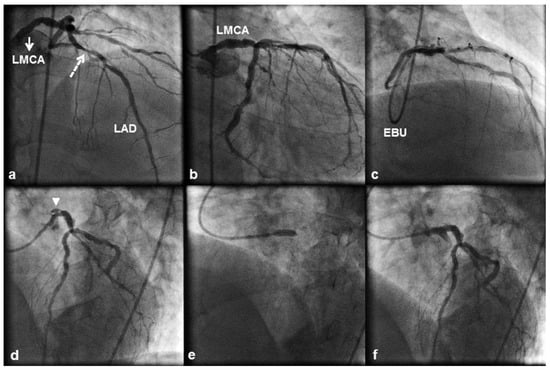

A 58 year old male patient with a history of hyperlipidaemia and cigarette smoking underwent transfemoral coronary angiography because of stable angina and ischaemia over the LAD artery territory, demonstrated with dobutamine stress echocardiography. Angiography showed diffuse nonobstructive LMCA disease (Figure 2a, b), significant proximal LAD disease (Figure 2a) and chronic occlusion of a left posterior descending artery with faint filling through bridging collaterals. Therefore, we proceeded with PCI to the LAD artery lesion. The LMCA was engaged with a 6 French EBU 4.0 guiding catheter, and a 3.5 × 13 mm DES was directly implanted across the lesion (Figure 2c). Shortly thereafter the patient complained of acute, severe chest pain, and after multiple views focal and persistent extraluminal contrast staining that was compatible with a type C ostial LMCA dissection (Figure 2d) was revealed. The dissection was directly stented with a 4.0 × 15 mm DES (Figure 2e). Stent postdilation was performed with a 4.5 × 15 mm noncompliant balloon with a good final angiographic result (Figure 2f). Postprocedural creatine kinase and creatine kinase MB isoenzyme levels were normal, and the patient was discharged home after a 2 day uneventful hospital course. He was prescribed life long dual antiplatelet therapy. He remained stable 3.0 years after stenting with Canadian angina class I and no evidence of a cardiovascular event.

Figure 2. (a) 10° right anterior oblique (RAO) 40° cranial view of the left coronary artery displaying significant proximal left ante- rior descending (LAD) artery disease (dashed arrow). The left main coronary artery (LMCA) (a,b) contained substantial ather- oma but no significant stenosis. (c) 40° RAO 40° cranial view obtained through a 6 French Extra Back-up (EBU) 4 guiding catheter showing the LAD artery stent deployment position. (d) 40° left anterior oblique (LAO) 20° cranial view after stenting displaying contrast outside the coronary lumen (“extraluminal cap”) at the LMCA ostium (arrowhead), which persisted after contrast had cleared from the coronary lumen (type C coronary dissection). (e) Stent deployment across the dissection. (f) 40° LAO 20° cranial view showing an optimal angiographic result with complete sealing of the dissection flap.

The RCA is the most frequently dissected vessel (84– 87% of the cases), followed by the LAD, left main coronary and LCx arteries [16,17]. Iatrogenic dissection of both the RCA and LMCA is mostly observed after inadequate alignment of a diagnostic or guiding catheter (1,2,4), yet the LMCA and RCA arise from their respective aortic sinuses at different angles: acute (range 20°– 55°) and almost perpendicular (range 60°–88°), respectively. This might render the LMCA less susceptible to catheter induced dissection by providing a better approach for catheterisation [17]. Three retrospective case series have reported the incidence of iatrogenic LMCA dissection during a coronary catheterisation procedure (PCI or diagnostic coronary angiography). Lee et al. [1] reported an incidence of 0.03% (10 cases out of 34 190 procedures), Cheng et al. [2] an incidence of 0.071% (13 cases out of 18 400 procedures), and Eshtehardi et al. [4] an incidence of 0.07% (38 cases out of 51 452 procedures) with a twofold greater incidence of iatrogenic LMCA dissection during PCI (0.1% of all PCIs) than during diagnostic coronary angiography (0.06% of all diagnostic coronary angiographies). Dissection of the LMCA is most frequently caused by inappropriate positioning of the diagnostic or guiding catheter, with an incidence of 61.5% in the study by Cheng et al. [2] where a 6 French catheter was used in 84.6% of the cases, the Kimny miniradial catheter in 61.5% of the cases and the left Judkins catheter in 30.8% of the cases. Balloon dilation near the LMCA bifurcation and stenting at the LAD artery ostium were the second and third most frequent causes of LMCA dissection in this study, with an incidences of 23.1% and 7.7%, respectively. In the study by Eshtehardi et al. [4], inappropriate positioning of a diagnostic catheter was implicated in 58% of the cases of LMCA dissection where the left Judkins catheter was used in 82% of the cases; inappropriate positioning of a guiding catheter was implicated in 16% of the cases of LMCA dissection where extra backup catheters (Amplatz left , EBU- or Q curve) were used in 56% of the cases. The second most frequent cause of LMCA dissection in this study was deep intubation of the guiding catheter during balloon retrieval, which was observed in 26% of the cases. In our first case, as shown in Figure 1b, the 6 French EBU 4.0 guiding catheter was non coaxially positioned and its tip abutted against the wall of the LMCA ostium without, however, causing pressure damping or ventricularisation. However, such a catheter position suggested that the catheter might have been “too short” for the patient and that a more coaxial LMCA engagement could have been achieved with an EBU 4.5 guiding catheter. Dissection of the LMCA occurred secondary to deep seeding of the guiding catheter and scraping of the LMCA wall during retrieval of the postdilating balloon. If we had disengaged the guiding catheter from the LMCA and pulling, to keep the catheter out of the LMCA ostium, had been more vigorous to withstand the resistance met during retrieval of the postdilating balloon, we would have prevented deep seeding of the guiding catheter and the resultant LMCA dissection. In our second case, the LMCA contained substantial, but nonobstructive atheroma. As shown in Figure 1d, the 6 French EBU 4.0 guiding catheter was non coaxially positioned with its tip pointing vertically against the roof of the LMCA. Accordingly, a hydraulic LMCA dissection might have been created during contrast injection. Keeping the catheter coaxially positioned during every minute of the procedure, avoiding contrast media injection in the presence of pressure damping or ventricularisation and gradual ramping of the injection are essential actions in order to minimise the risk of LMCA dissection.